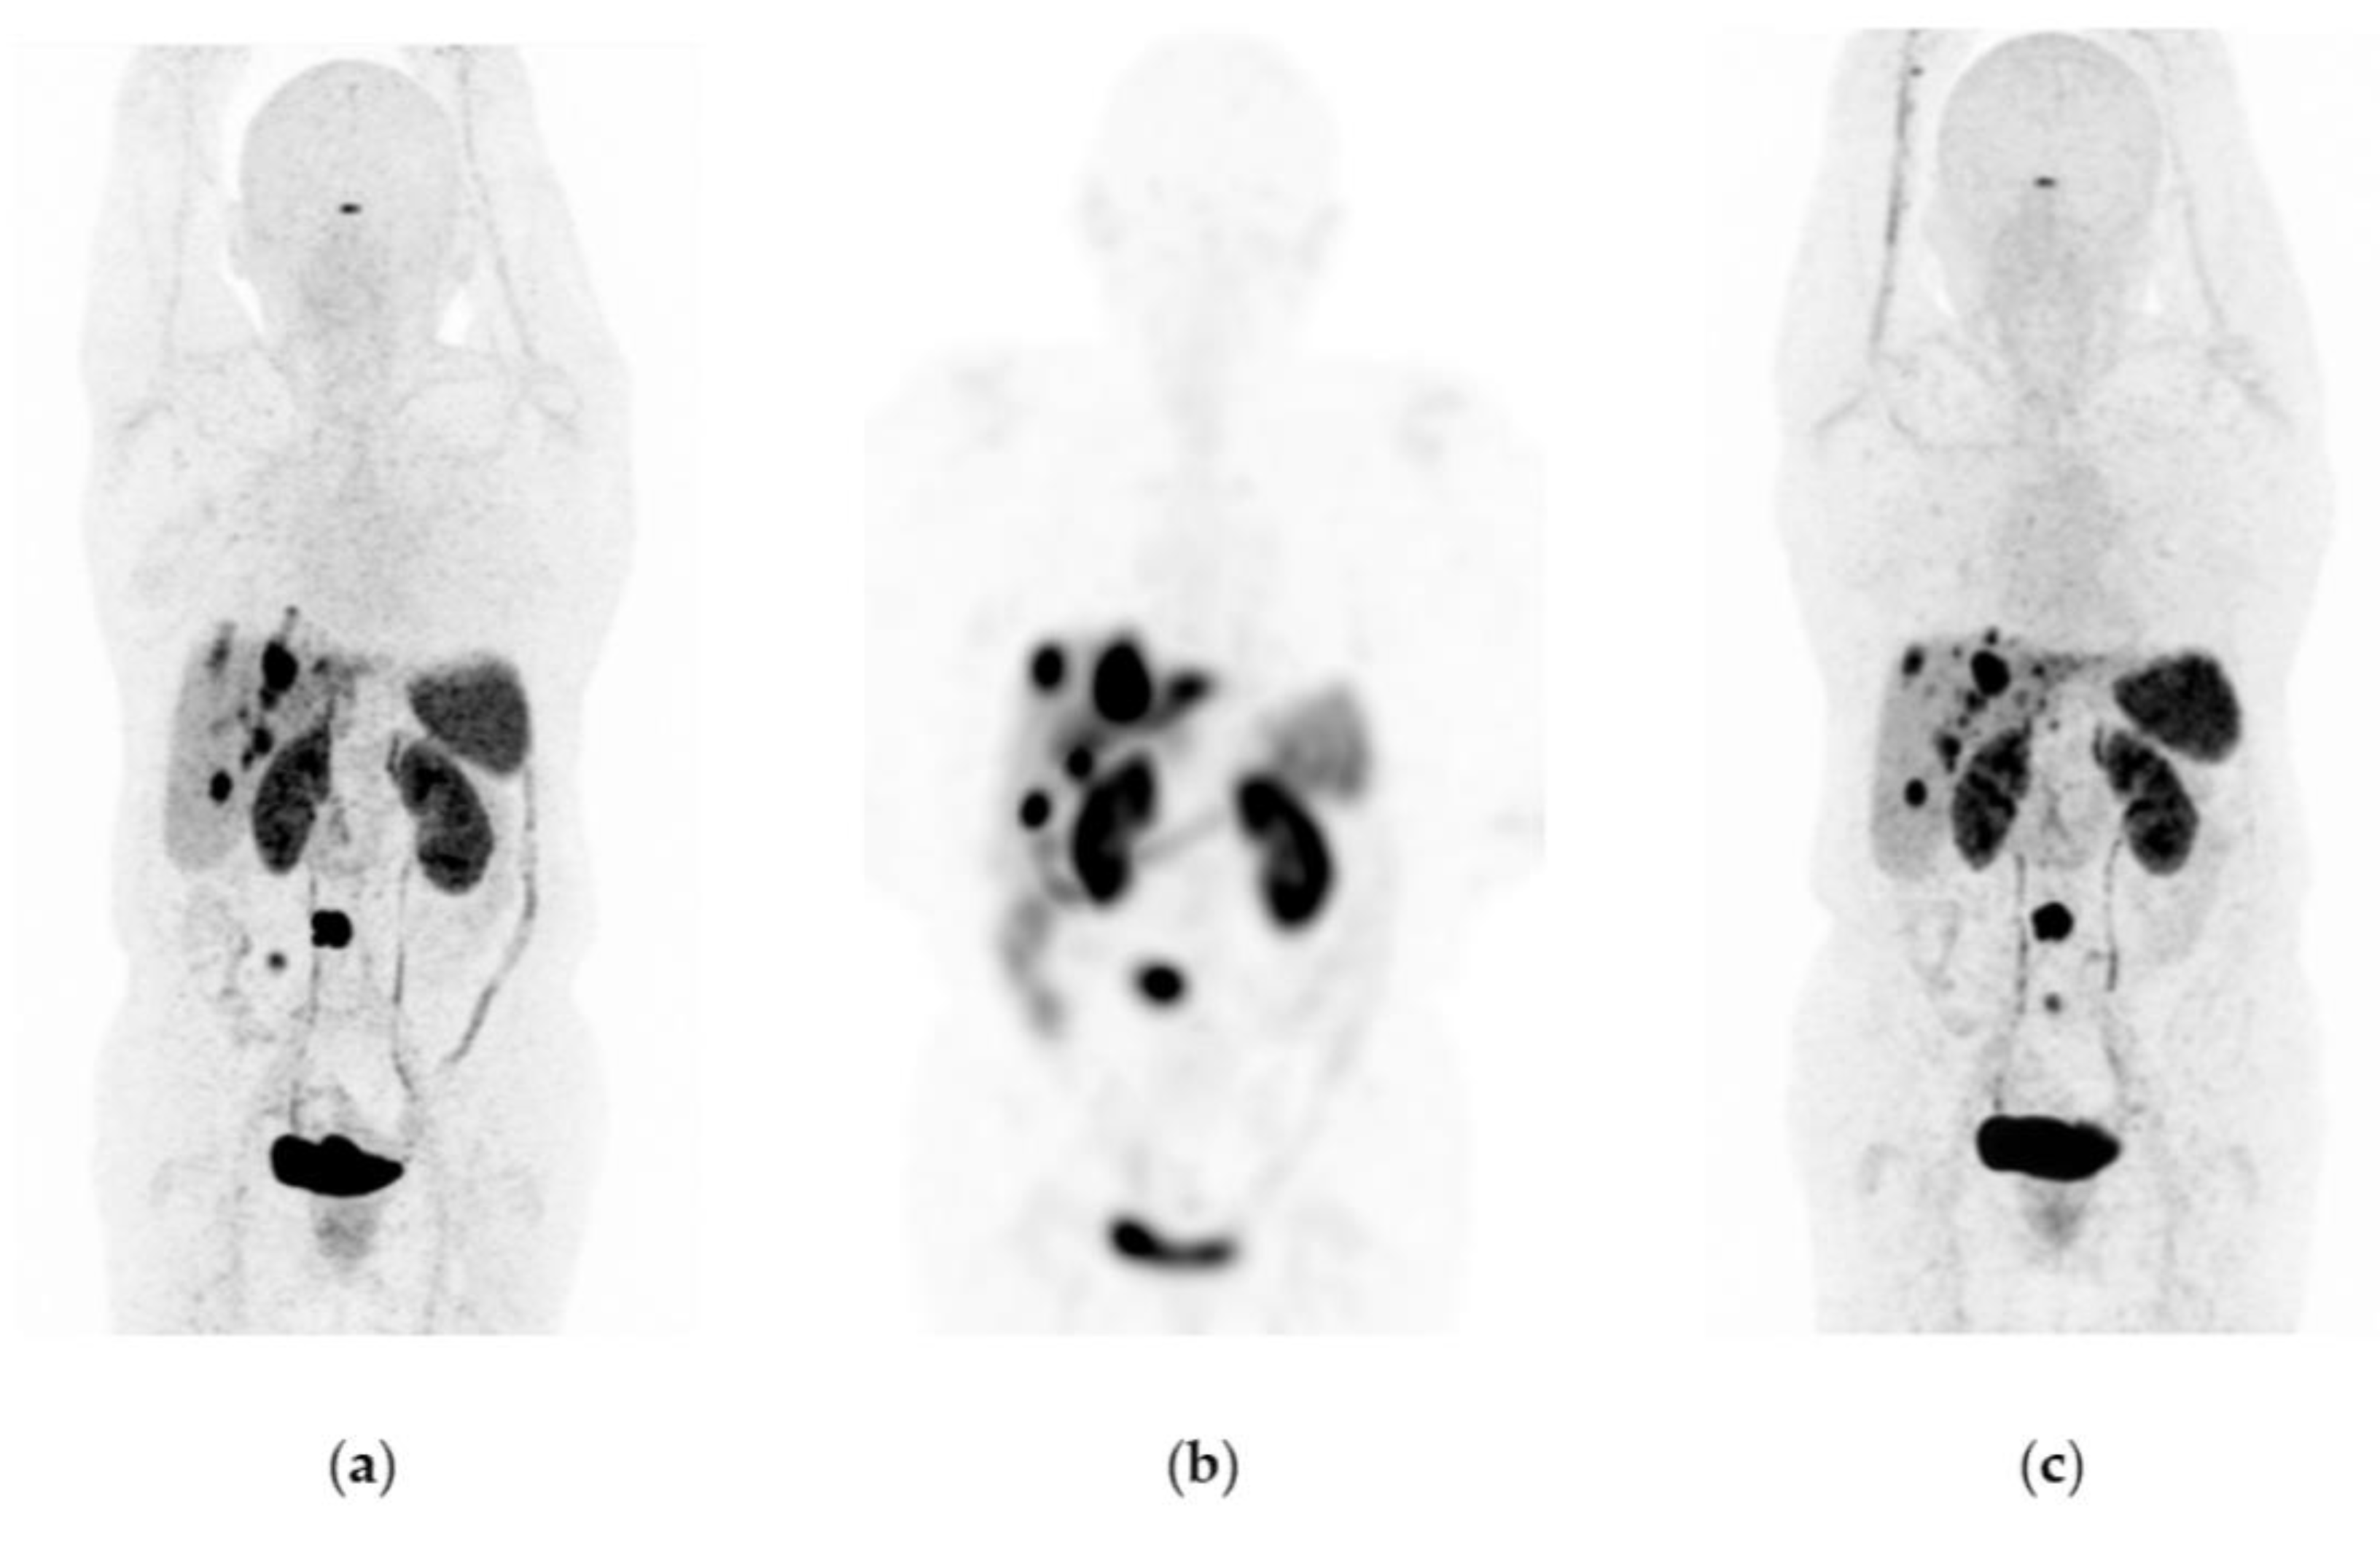

Figure 3. Patient with progressive and metastatic castration-resistant prostate cancer (mCRPC): (a) 68Ga-iPSMA PET/CT imaging before 177Lu-iPSMA therapy; initial levels of hemoglobin (11.1 g/dL), leucocytes (4900/µL), creatinine (0.88 mg/dL), platelets (115,000/µL), and serum PSA (84.7 ng/mL). (b) 177Lu-iPSMA SPECT imaging (first dose). (c) 68Ga-iPSMA PET/CT imaging 10 months after the first 177Lu-iPSMA dose was administered; levels of hemoglobin (10.1 g/dL), leukocytes (2100/µL), creatinine (0.91 mg/dL), platelets (87,000/µL), and serum PSA (7.7 ng/mL). The patient responded partially to 177Lu-iPSMA therapy (four doses every six weeks; 7.4 GBq/dose).

177Lu-iPSMA showed an overall response rate of 36.6% (Table 2). Figure 2 and Figure 3 show typical clinical cases of complete response (disappearance of all lesions or adenopathies less than 10 mm short axis) and partial response (decrease of at least 30% in the sum of the largest diameters of lesions compared with the baseline study) after 177Lu-iPSMA therapy. In addition, the reduction of large tumors and multiple metastatic lesions are proof of the high specificity and molecular recognition of 177Lu iPSMA by PSMA at the tumor cell level (Appendix A) (Figure A1, Figure A2 and Figure A3).